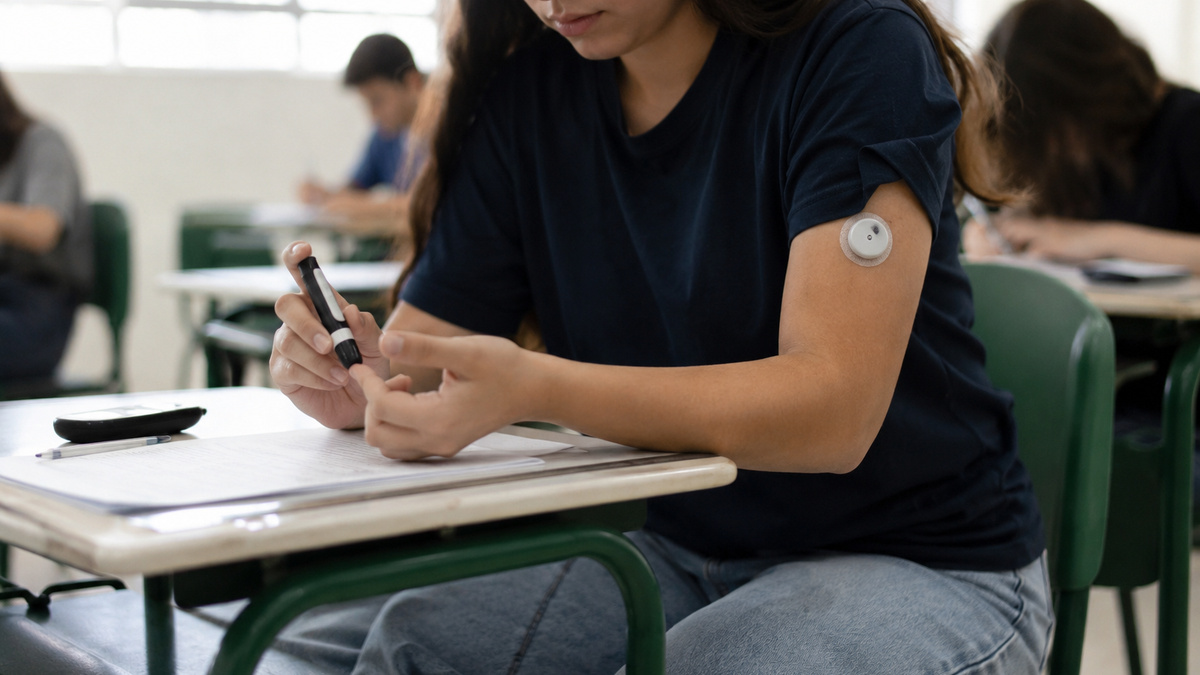

Pausa para medir glicose no trabalho e aplicar insulina durante uma prova? Entenda a nova lei do diabetes tipo 1 que promete mexer com empresas, escolas e concursos públicos em todo o Brasil